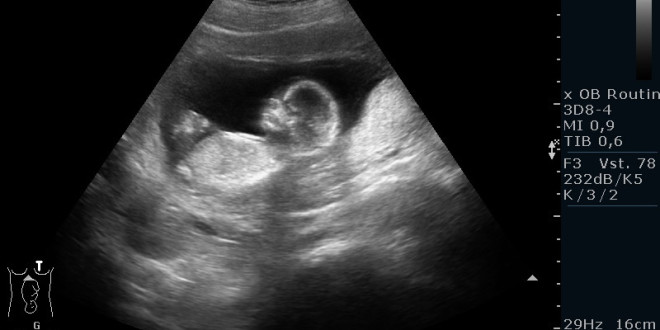

Frühschwangerschaft:

Ultraschall_19